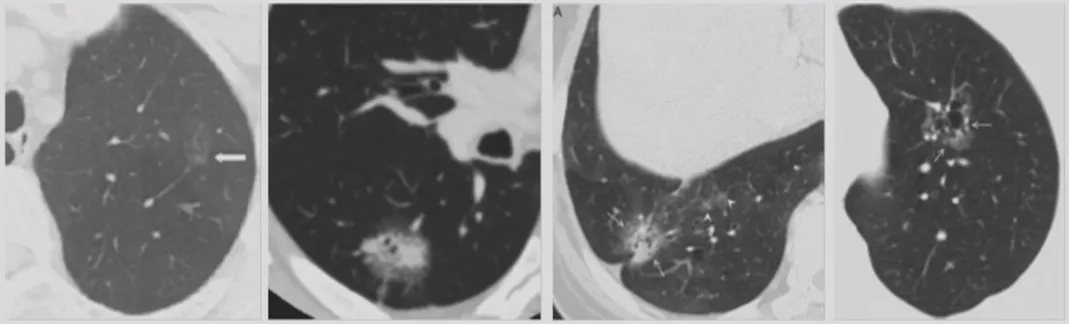

CT随访

1)病灶大小无变化、实性成分增多

这个结节大小没有太大变化,实性成分增多,这不是一个好征象,可以考虑手术。

2)病灶缩小、出现实性成分

容易被大家忽略的是结节的大小变小,但实性成分增多,值得大家重视。不要认为结节变小了就一定是良性。